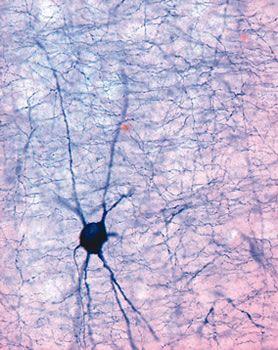

The Leica VT1000 S vibrating blade microtome is the instrument of choice for high-quality sectioning requirements in neurophysiology, neuropathology experimental pathology ), Botany (roots and plants) and Industry (foams).

When sectioning fixed tissue for specific neuropathology tests the Leica VT1000 S consistently provides high-quality sectioning results.